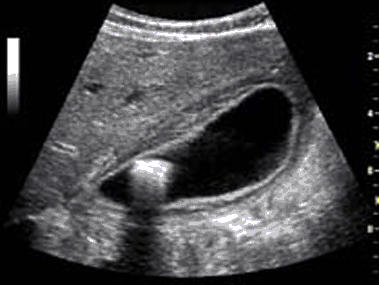

Para hacer el diagnóstico de enfermedad vesicular el estudio de elección es el Ultrasonido, y además de cálculos se pueden encontrar otras alteraciones como tabiques congénitos y lodo biliar que también provocan la inflamación de la vesícula.

ULTRASONIDO QUE  DEMUESTRA LODO BILIAR Y UN TABIQUE INTRAVESICULAR